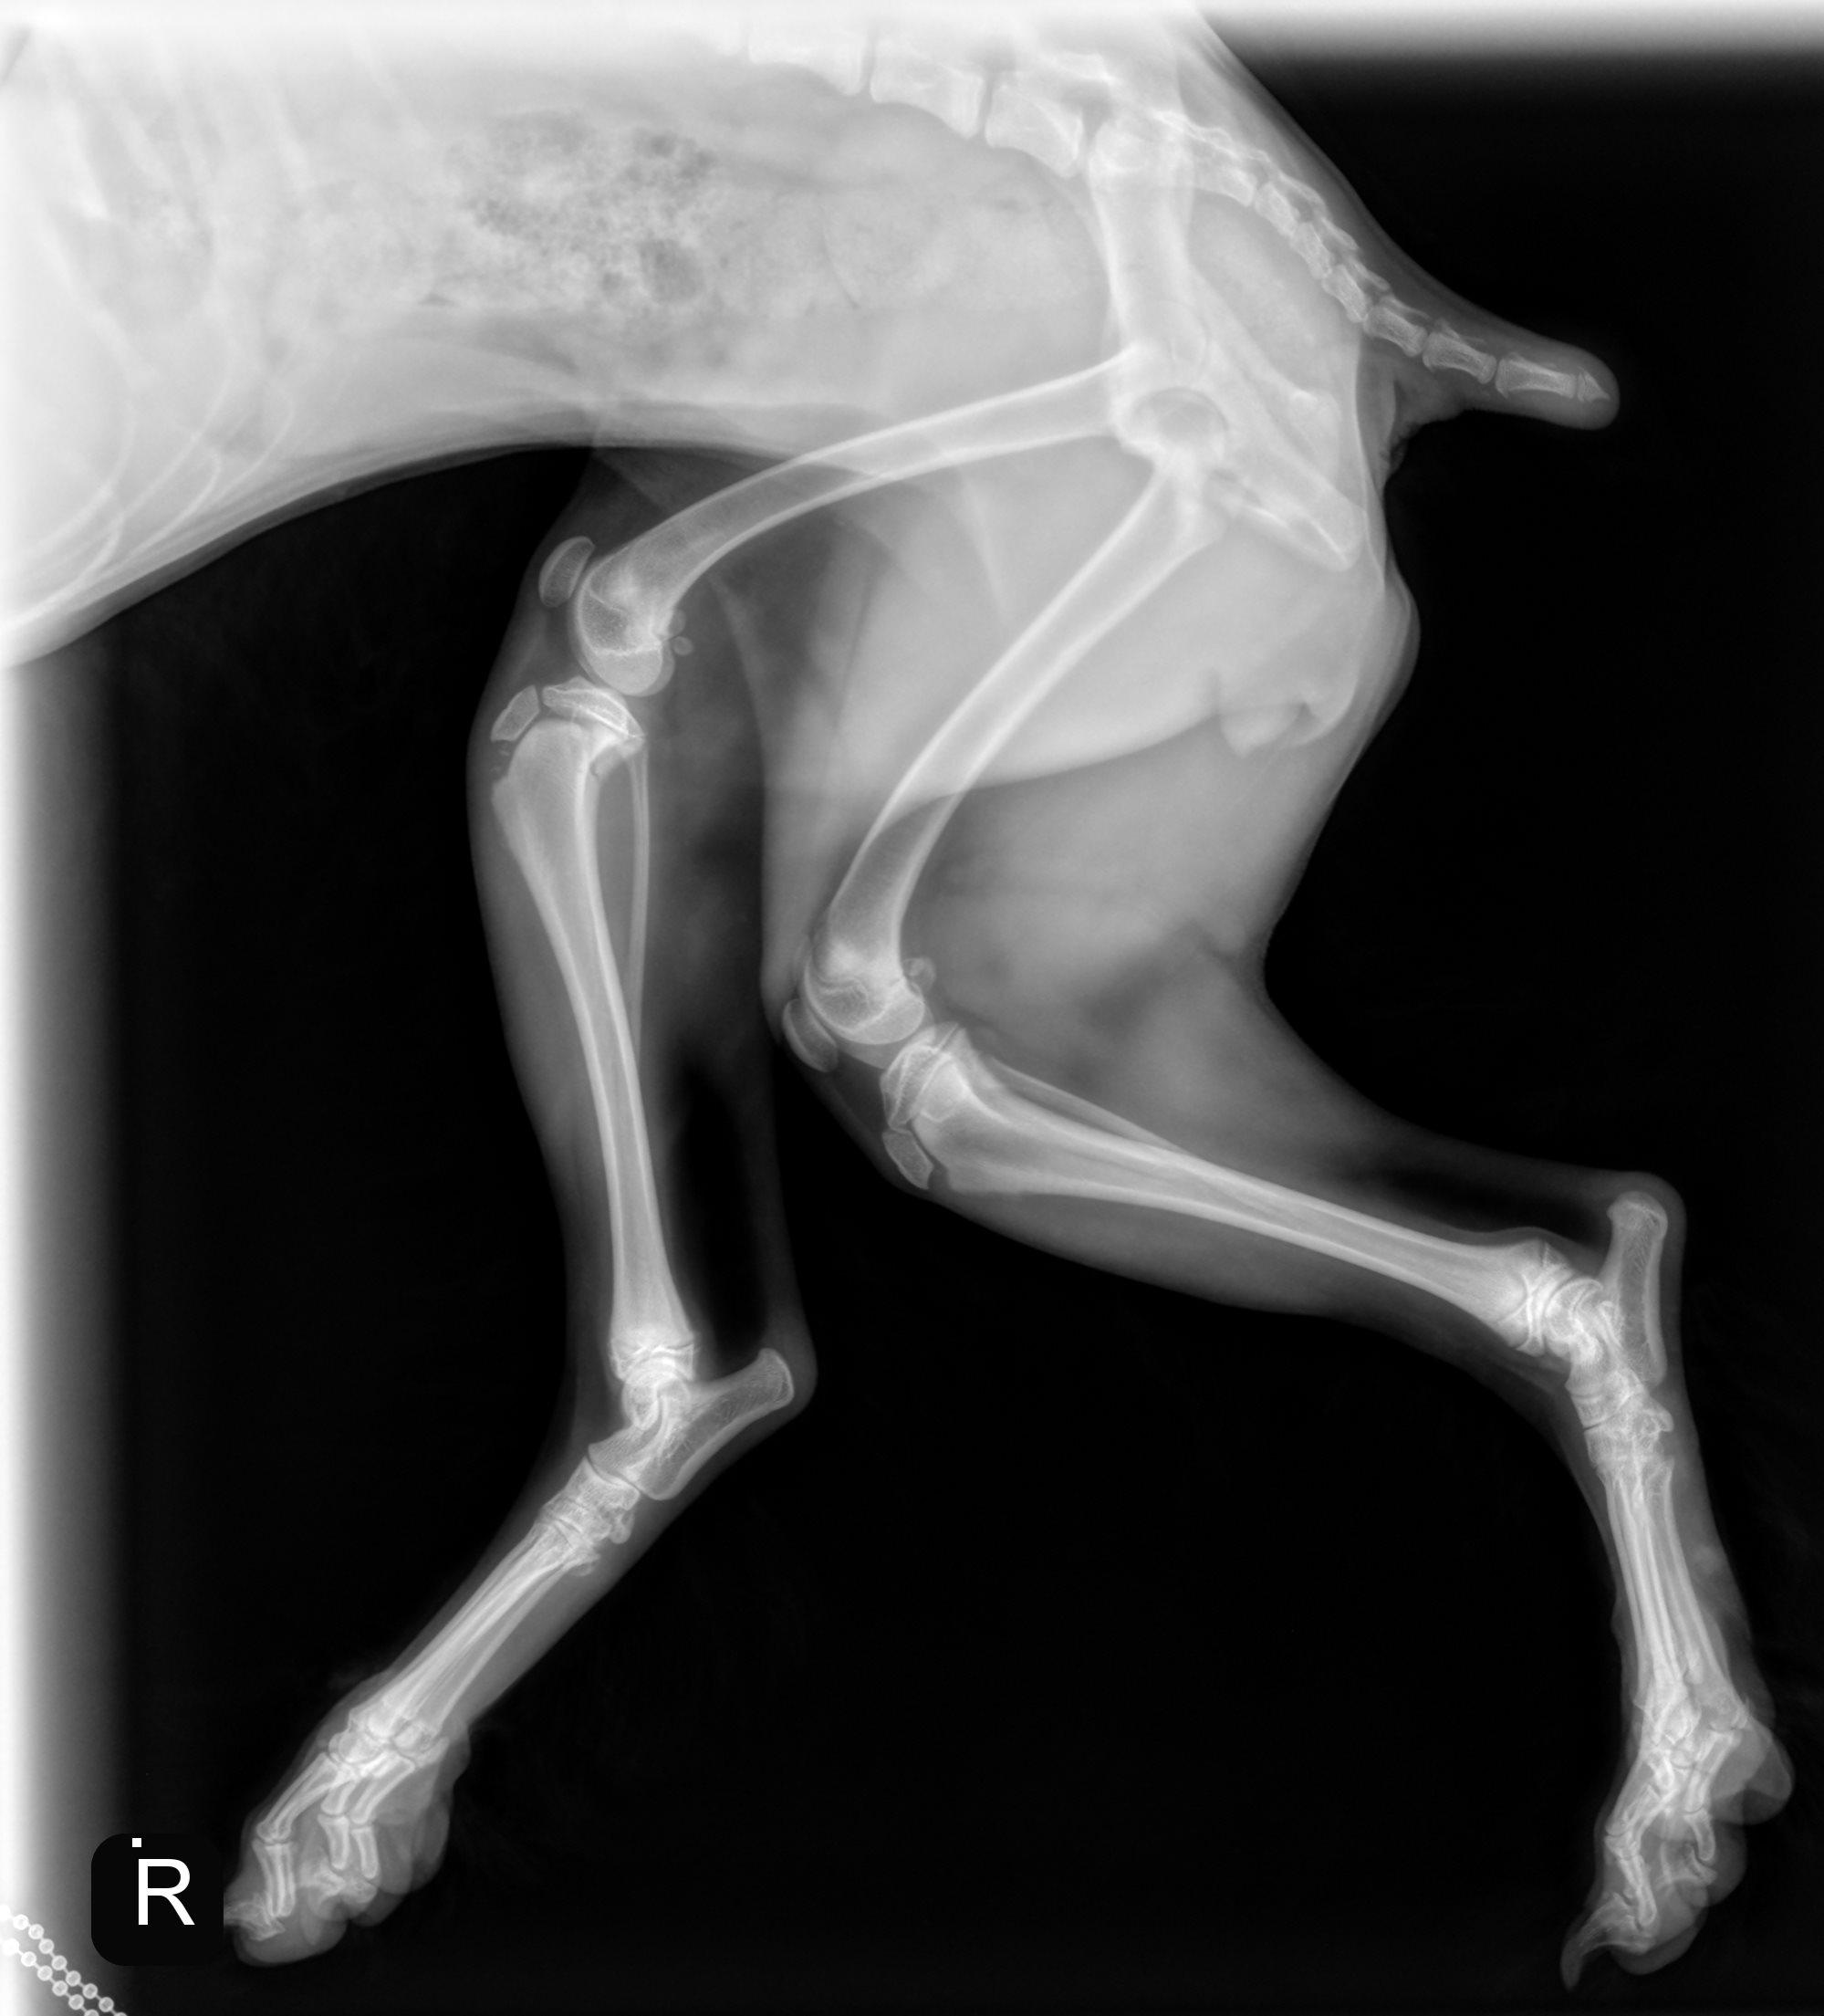

Hieronder vind je de 3 röntgenfoto’s van de achterpoten en bekken. Gebruik de pijltjes om erdoor te schuiven, of klik op de foto om te vergroten.

Er is een avulsiefractuur van de tuberositas tibiae aan de rechterpoot. De tuberositas tibiae is proximaal verplaatst en er zijn minstens enkele kleine botfragmenten zichtbaar ter hoogte van de fractuurplaats. Gelijktijdig is er een Salter-Harris type II fractuur van het caudo-proximale deel van de tibia, het best zichtbaar op de laterale opname. Het overige deel van de achterpoten is radiografisch binnen de normale grenzen.

Avulsiefractuur van de rechter tuberositas tibiae met kleine botfragmenten. Chirurgisch consult wordt aanbevolen.